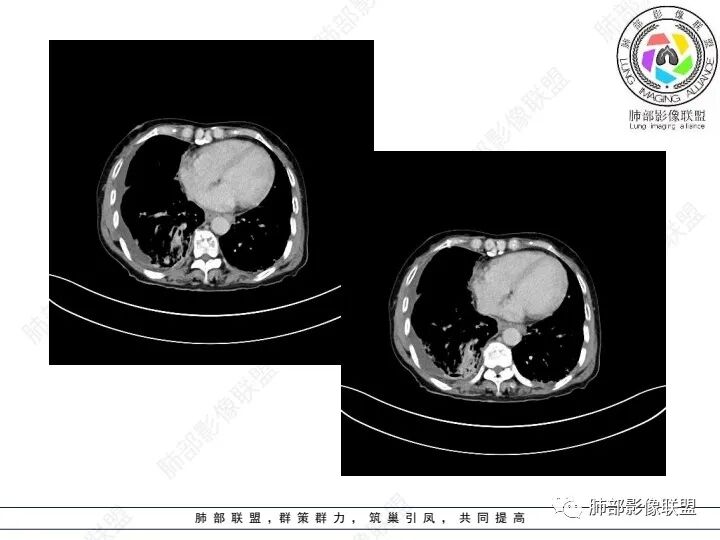

双肺间质性改变,右肺下叶支气管环形增厚,支气管变窄,周围见钙化影,右肺下叶软组织占位,明显的坏死,明显环形强化,两侧肺门及气管隆突下淋巴结肿大。右侧胸腔积液,肝脏周围少量腹腔积液,老年女性患者腹痛便血,Ca125明显增高。考虑1一元论:腹腔恶性肿瘤(胃肠道或卵巢来源)肺内及胸膜腹膜转移;2二元论:右下肺粘液表皮样癌/腺样囊性癌,腹腔胃肠道或卵巢来源肿瘤。

老年女性,右肺下叶后基底段实性肿块,边缘强化明显,坏死,形态湖泊状,坏死轮廓不清,右肺门下方淋巴结肿大融合,包绕右肺下叶支气管血管束开口,右肺脏层及叶间胸膜多发转移强化结节,右侧胸腔积液,肺气肿背景,支持恶性,肺腺Ca,右肺下叶肿块经皮肺穿刺活检,另消化道岀血,Ca125值明里高,与肠Ca,补充腹部CT平扫及增强和肠镜检查,肠Ca右肺转移待排。

女,69,腹痛、便血4小时。CA125增高。胸部CT:肺气肿背景。右下叶不规则肿块影,处于外周气肿带与正常肺交界区,强化不均匀,中心有坏死;纵隔及肺门多发肿大淋巴结、融合,包绕支气管,部分钙化、环形强化;右下支气管周围管壁增厚伴环形钙化、狭窄。右侧胸膜多发结节灶,增强后明显强化,右侧胸腔积液。考虑恶性,右下肺腺Ca多发转移?转移瘤?鉴别TB、IgG4等。

3、胸部增强CT示右肺下叶脊柱旁不规则软组织肿块,侵及壁层胸膜外,密度不均匀,不均匀强化,中心低密区可疑坏死,右侧胸腔积液、胸膜结节影或结节样增厚,增强扫描可见强化,右侧肺门及纵隔内可见淋巴结肿大、融合,右侧中尖段支气管及右肺下叶支气管受侵,管腔狭窄。

4、综上,老年男性,CA125升高,右肺下叶肿块侵犯胸壁,伴纵隔、右肺门及纵隔淋巴结肿大,右侧胸腔积液、胸膜增厚伴结节影,强化明显,应该为一较典型的肺癌伴肺胸膜腔及肺门纵隔淋巴结转移,尤其是肺腺癌。